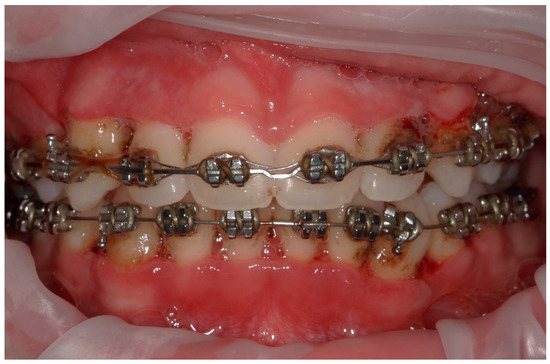

4.1. Case 1

4.2. Case 2